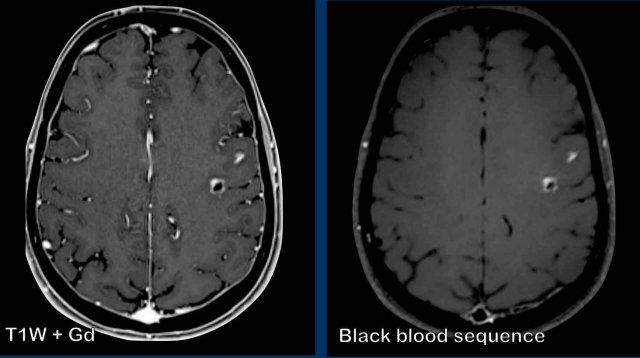

Các hình ảnh này của bệnh nhân ung thư phổi di căn. Ghi nhận hai tổn thương di căn ngấm thuốc tại bán cầu não trái.

Trên chuỗi xung T1W có tiêm thuốc tương phản từ Gadolinium, các mạch máu cũng ngấm thuốc mạnh khiến việc phát hiện các tổn thương di căn trở nên khó khăn.

Trên chuỗi xung “black blood” (xóa tín hiệu máu), tín hiệu của máu trong lòng mạch bị triệt tiêu, giúp nhận diện các tổn thương di căn ngấm thuốc dễ dàng hơn.